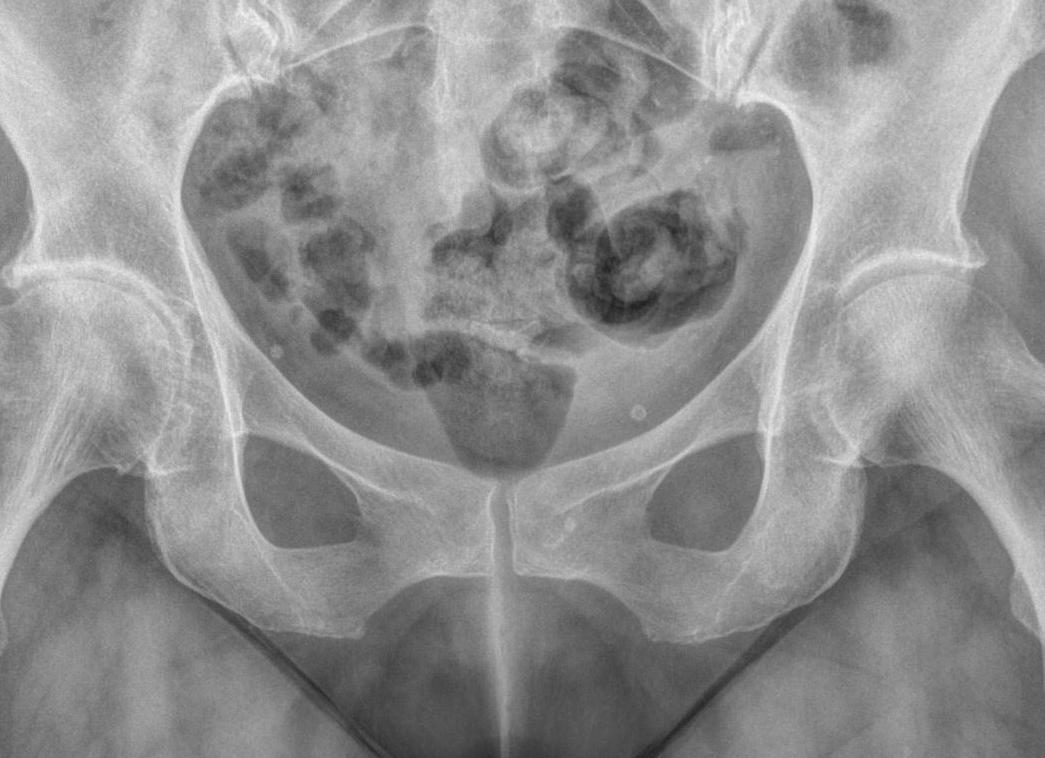

Рентген тазобедренного сустава дает возможность четко оценить состояние плотных тканей. Кроме этого диагност осмотрит и прилегающие ткани в области седалищной, подвздошной, лобковой и бедренной кости. Для получения лучших результатов диагностики показано выполнение снимков в нескольких проекциях. Те участки, которые находятся рядом с просвечиваемой зоной, обязательно закрывают свинцовыми пластинами, что позволяет уберечь их от негативного воздействия рентгеновских лучей.

Сразу необходимо сказать, что правильность выполнения рентгенографии и четкость снимков зависит от квалификации диагноста, который делает процедуру. Все дело в том, что однотипные патологические изменения могут быть интерпретированы по-разному. Именно поэтому за основу врачи всегда берут жалобы пациента, то есть анамнез, а также историю болезни. Любой патологический процесс имеет свои характерные особенности, поэтому на снимках можно видеть:

• отломки костных структур – если было подозрение на нарушение целостности тазобедренного сустава;

• если пациент жаловался на незначительную травму, тогда врач увидит смещение поверхности сустава, что говорит о вывихе или подвывихе;

• при остеоартрозе всегда отчетливо видны остеофиты, а также смещение щели сустава;

• когда прогрессирует остеопороз, диагност отметит снижение уровня плотности кости, а также истончение костной структуры;

• если прогрессирует асептический некроз, то рентген покажет наличие очагов отесклероза и костную регенерацию;

• при опухолевых процессах всегда будет видно затемнение, говорящее о наличии очагов.

Качество расшифровки полученных данных зависит от квалификации доктора и правильности проведения процедуры. Опытный врач без проблем отличит рентгеновский снимок здорового тазобедренного сустава от рентгена с патологией. Важно понимать, что несмотря на большое количество возможных заболеваний данного суставного сочленения, на снимке встречается ограниченный ряд изменений:

• отломки костей встречаются при травматических переломах;

• при подвывихе и вывихе основной рентгенологический признак – смещение поверхностей сустава относительно друг друга;

• остеоартроз характеризуется появлением остеофитов (локальные разрастания костной ткани) и уменьшением просвета суставной щели;

• истончение костной ткани со снижением ее плотности – специфический признак остеопороза;

• дисплазия структур тазобедренного сочленения на рентгене проявляется отсутствием части головки бедренной кости или вертлужной впадины на тазе;

• опухолевые заболевания характеризуются объемными образованиями неправильной формы.